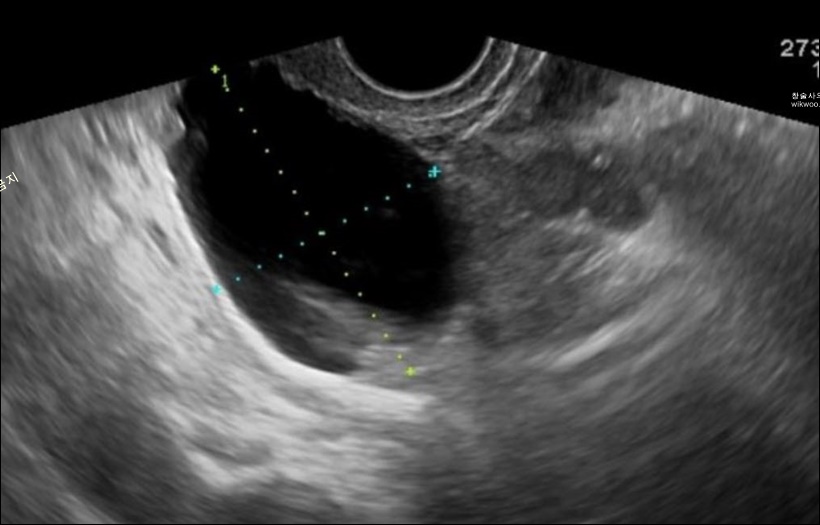

아래는 실제 사례인 후기들입니다.